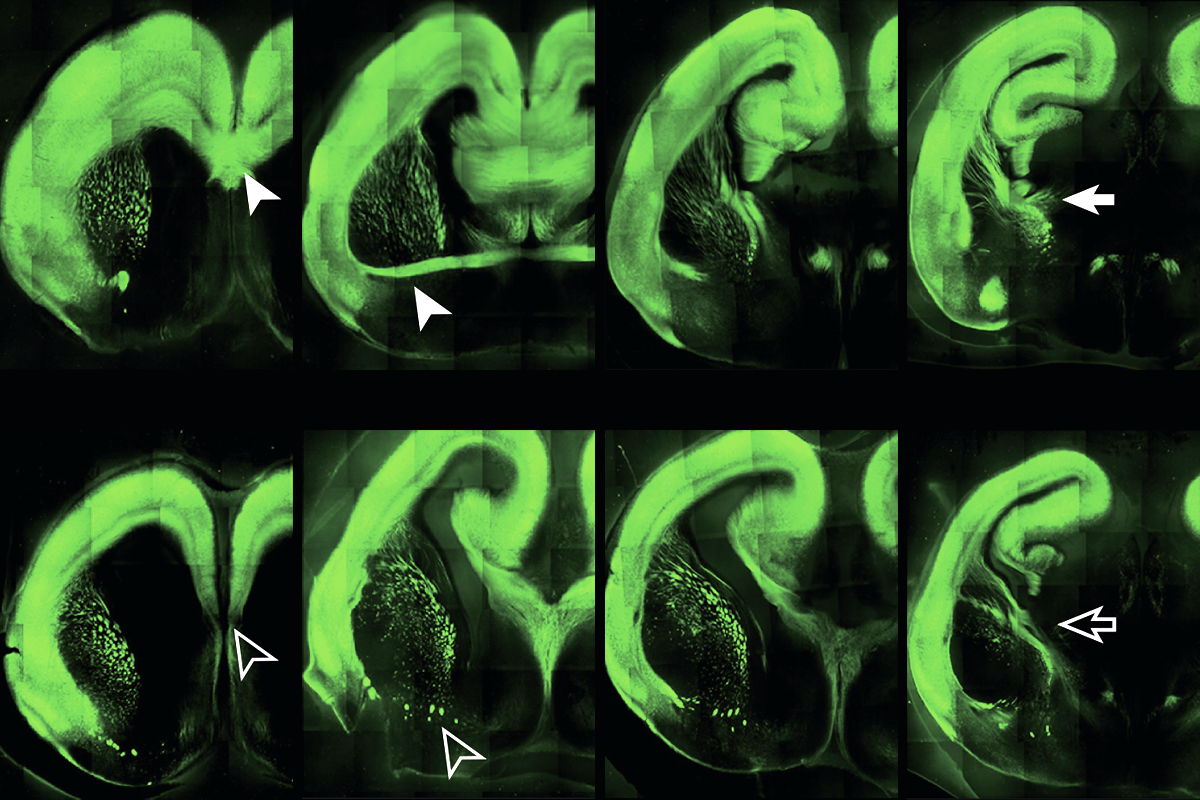

Thinning out: Mice missing the ZBTB18 gene (bottom panels) show altered brain structure and connectivity (coronal images with green-stained axonal projections) when compared with wildtype mice (top panels).

Brain evolution: Molecular and cellular regulatory components that support neuronal communication across the layers of the cerebral cortex distinguish mammalian brains from non-mammalian ones, a new study details. The investigators focused on the many types of excitatory projection neurons and their genes—and specifically zeroed in on the transcription factor ZBTB18, which is implicated in autism and intellectual disability. Deletion of ZBTB18 in mouse excitatory projection neurons decreased molecular diversity and connectivity within the brain, reminiscent of older evolutionary brain structures. The authors surmise that although the complexity in the mammalian brain has advantages (and is highly conserved), it may also “render them more susceptible to various neurodevelopmental and neuropsychiatric disorders.”